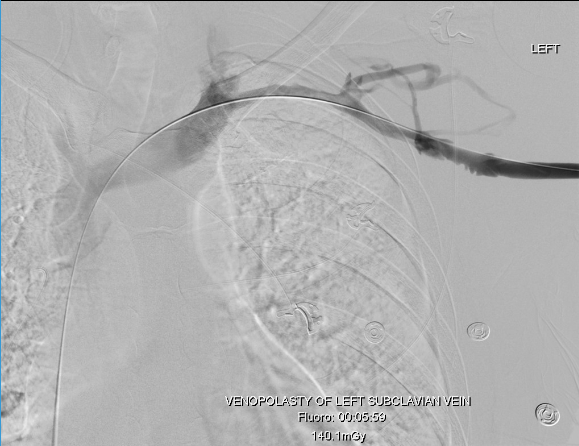

Recently, I saw a case presentation uploaded to LinkedIn of a subclavian venous stenosis treated with balloon venoplasty and a stent for venous congestion of the arm. The images were beautifully clear. The stenosis was at the thoracic outlet. The comments were generally favorable, including congratulations for a nice case, but I had to put in my two cents: The thoracic outlet is a terrible place for a stent due to external compression, and once occluded, a stent in the venous position is a permanent obstruction. The justification was that the patient did not want surgery and there were no surgeons who did first rib resections where the post author worked. I refrained from commenting something about primum non nocere.

This patient from the images above is a middle aged man who competes in triathalons and who noted sudden onset of discomfort and heaviness and pain in his left arm. Ultrasound revealed DVT in his axillosubclavian veins extending into his brachial veins and he was started on anticoagulation. He had been on anticoagulation for about a month by the time he came to my clinic. On examination, he had a prominent superficial veins on his shoulder, but otherwise had a normal examination. He did not have arterial obstruction on TOS (thoracic outlet syndrome) maneuvers and had no neurologic symptoms. I recommended first rib resection.

The patient did well, recovering much of his range of motion quickly with the help of physical therapy. He was taken to the angio suite and underwent venography shown below. There is an occlusion of the subclavian with outflow via collateral veins. Not seeing collaterals is as important as seeing a good angiographic result. pre intervention

Venoplasty was done to 8mm -I try not be overly aggressive here, just to break the strictures that caused the balloon to have a waist in two sections. The final result is below, with the absence of the venous collaterals. If they were still present despite an angiographically satisfactory result, I would perform IVUS to see what the problem was. In no circumstances would I place a stent at this juncture -my plan is to keep the patient on anticoagulation for 3 more months.